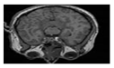

This section contains extensive performance evaluation findings for the three suggested approaches. The developed systems were tested over Matlab environment. As shown in Figure 6, the suggested encryption techniques have been tested for color, grayscale, and medical photos, each of which is 256 × 256 pixels in size, with watermarks of 64 × 64 pixels.

Figure 6.

Color, grayscale and medical images and watermarks.